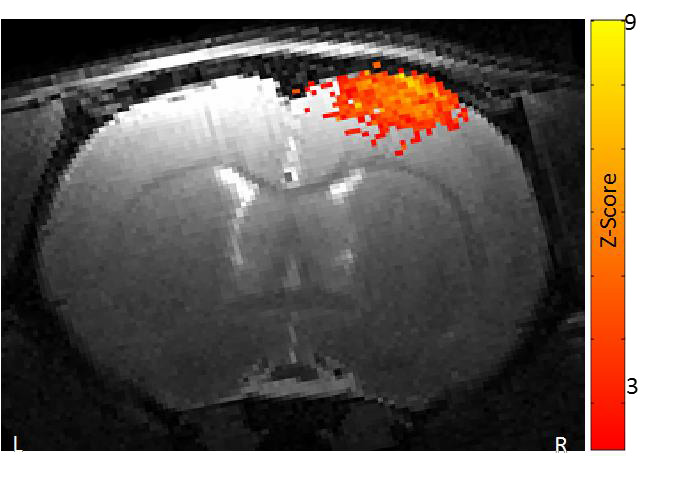

2、功能磁共振成像

功能磁共振成像需要最强的磁场,最好的梯度和最稳定的系统。布鲁克优异的梯度系统确保在单次激发下得到整个脑部的图像。功能卓越的匀场单元最大程度地消除平面回波成像几何形变。特有的频率和相位稳定性保证多次激发EPI扩散张量成像的品质。高分辨率的功能磁共振成像可以深入洞察大脑的功能反应。

小鼠脑部的功能磁共振成像: